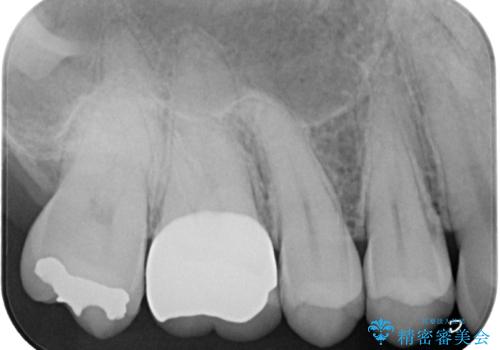

- 以前他院で治療した銀歯が外れてしまったとのことで来院された患者様です。

精査の結果、歯の神経は問題ないですが、欠損している範囲が大きいため部分的な詰め物では脱離や破折のリスクが高いため、オールセラミッククラウンによる補綴治療を行っていくこととしました。

適合の良い治療は再度虫歯になるリスクが低いです。